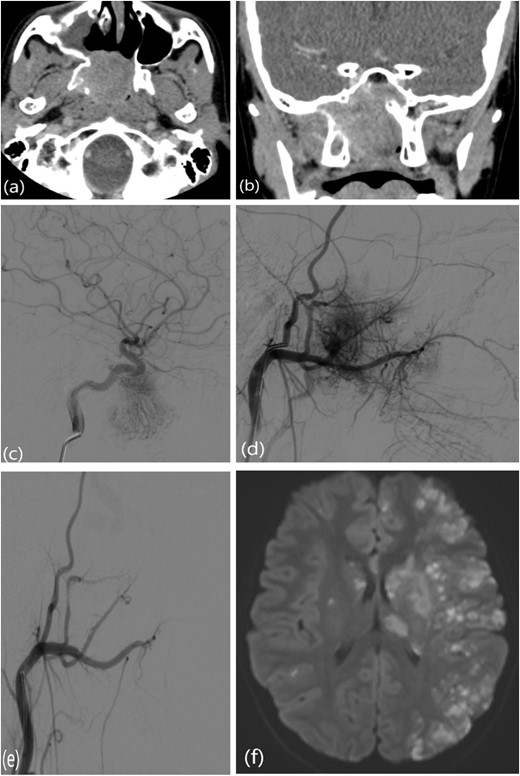

A 9-year-old previously healthy male was referred due to left nasal blockage and mild intermittent epistaxis persisting for 6 months. Nasal endoscopy revealed a clearly evident pinkish mass in the left nasal cavity. Non-contrast Computed Tomography (CT) of the paranasal sinuses (Fig. 1a and b) demonstrated a large, expansile, and ill-defined soft tissue mass with its epicenter in the left nasal cavity and nasopharynx. It extends to the left pterygopalatine fossa and the pterygomaxillary fissure, reaching the masticator space. The mass caused significant bone remodeling and expansion, with some erosions noted at the body and the left greater wing of the sphenoid bone, as well as the medial and lateral pterygoid plates. Additionally, the mass was seen extending to the lateral walls of the maxillary and ethmoid sinuses, bilateral sphenoid sinuses, and the inferior bony orbital wall. Contrast-enhanced Magnetic Resonance Imaging (MRI) showed a predominantly left-sided nasopharyngeal mass measuring 6.9 × 5.9 × 5 cm with increased vascularity (Fig. 1c). The mass replaced the left maxillary antrum, posterior ethmoid air cells, and sphenoid sinuses and invaded the left cavernous sinus (Fig. 1d). A pre-operative left ICA angiogram demonstrated the tumor’s blood supply originating from the vidian artery and inferolateral trunk, with the main supply arising from branches of the left internal maxillary artery (IMA). The vascular branches feeding the tumor from both IMAs were embolized.

(a) Axial non-contrast CT of the paranasal sinuses showing a soft tissue mass obliterating the posterior aspect of the nasal cavity, with extension and remodeling of the left pterygopalatine fossa into the infratemporal fossa. (b) Coronal image demonstrating superior extension into the left sphenoid sinus and left inferior orbital fissure. (c) Coronal T2-weighted MRI showing a large JNA with heterogeneous signal intensity and multiple flow voids consistent with hypervascularity. (d) Post-contrast coronal T1-weighted MRI demonstrating avid contrast enhancement and invasion of the left Meckel’s cave and cavernous sinus (arrow).